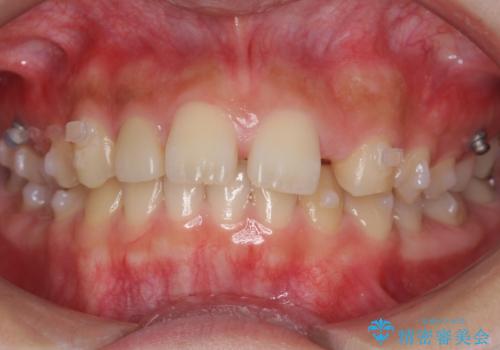

- インビザライン

- 前歯の並びを主訴に来院。

前歯が出ており、また、左上の側切歯が1本生まれつき少ない状態でした。

また、右の奥歯の関係も上が前にある状態で大きくずれていました。

臼歯関係は無理に1級にしようとすると抜歯が必要になります。

今回は左右とも1歯対2歯の関係であるため、それは変えずに前歯を可及的にひっこめて足りない部分をブリッジで補う治療としました。